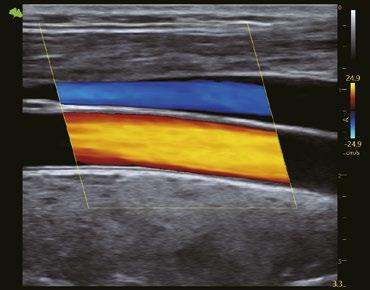

Karotis-CF

Echtzeit- und automatische Messung der anteriorenund postterioren Intima-Media.

Erkennung der Fließgeschwindigkeit des Blutes. Es ermöglicht eine feinere Diagnose, bei besonders schwierigen Untersuchungen des Blutflusses.